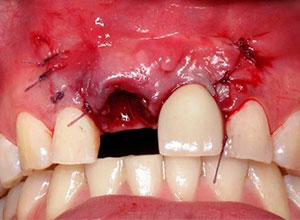

Decidimos hacer una corticotomia alveolar, dejando tejidos blandos en su lugar y cambiar la corona de cerámica por una corona de acrílico para cementar bien los brackets y poder empezar con la distracción.

Después de la corticotomia dejamos un tiempo de siete días para que se organizaran las células tisulares.

Se empezó a hacer la distracción, primero con un arco recto y posteriormente con elásticos haciendo el recorte con el borde incisal conforme se va bajando el implante con el bloque óseo.